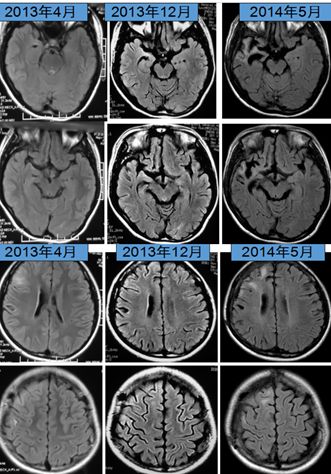

女患,15岁,主因双眼上翻,下颌阵挛2天来诊,伴发热,体温38-39度,发作性左侧上下肢、左侧口角强直-阵挛。入院查体:记忆力较前明显下降, 左侧肢体轻偏瘫(左上肢4+,左下肢5-)。

2年后,行“右侧额叶病变切除+右前颞叶切除+皮层热灼术”,持续3个月无发作。随后再次发作,表现为:间断出现左上肢或左下肢强直-阵挛(每次数秒至十余秒)。1年后出现左侧面肌、左手指、左脚趾呈近持续性抖动,清醒期明显,睡眠中基本消失。

诊断依据:①右侧半球;多灶性,轻偏瘫,认知下降;②视频脑电图(VEEG):EPC,PET:右侧半球代谢减低;抗癫痫药物疗效差;③术后病理:脑组织小胶质细胞和T细胞浸润。

Rasmussen脑炎:为单侧性大脑半球受累为主的进展性疾病,常规抗癫痫药物治疗无效,局灶性发作为其主要特点,部分性癫痫持续状态(EPC)为其发作的主要表现形式,多伴有受累侧半球相关的运动和认知功能减退。RE主要的病理特点:局限于受累大脑半球的炎性疾病,以T细胞浸润、小胶质细胞增生、小胶质结节形成,以及随后出现的神经元脱失、星形细胞增生等为主要表现形式。MRI特点岛叶及岛叶周围出现轻度局灶性大脑皮质萎缩;同侧脑室扩大;大脑皮质和(或)皮层下T2和FLAIR像的高信号;尾状核头部信号增高或萎缩。在上述改变未发生之前可先出现一过性大脑皮质局部肿胀。